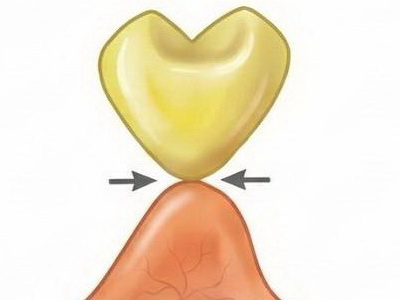

Răng giả nhịp cầu dạng chóp (Conical Pontic / Heart Shaped)

- Tiếp xúc: Răng giả có mặt đáy nhọn, dạng chóp hoặc hình tim, chỉ chạm vào trung tâm đỉnh sống hàm tại một điểm nhỏ.

- Đặc điểm: Tiếp xúc niêm mạc tối thiểu, để lại khoảng hở lớn ở các vùng kẽ.

- Thực tế trong lâm sàng: Rất dễ vệ sinh nhờ diện tiếp xúc nhỏ. Tuy nhiên thẩm mỹ kém và có thể dễ mắc thức ăn, nên chủ yếu dùng cho răng sau (răng cối) – nơi thẩm mỹ không phải ưu tiên và sống hàm mỏng, dạng lưỡi dao.